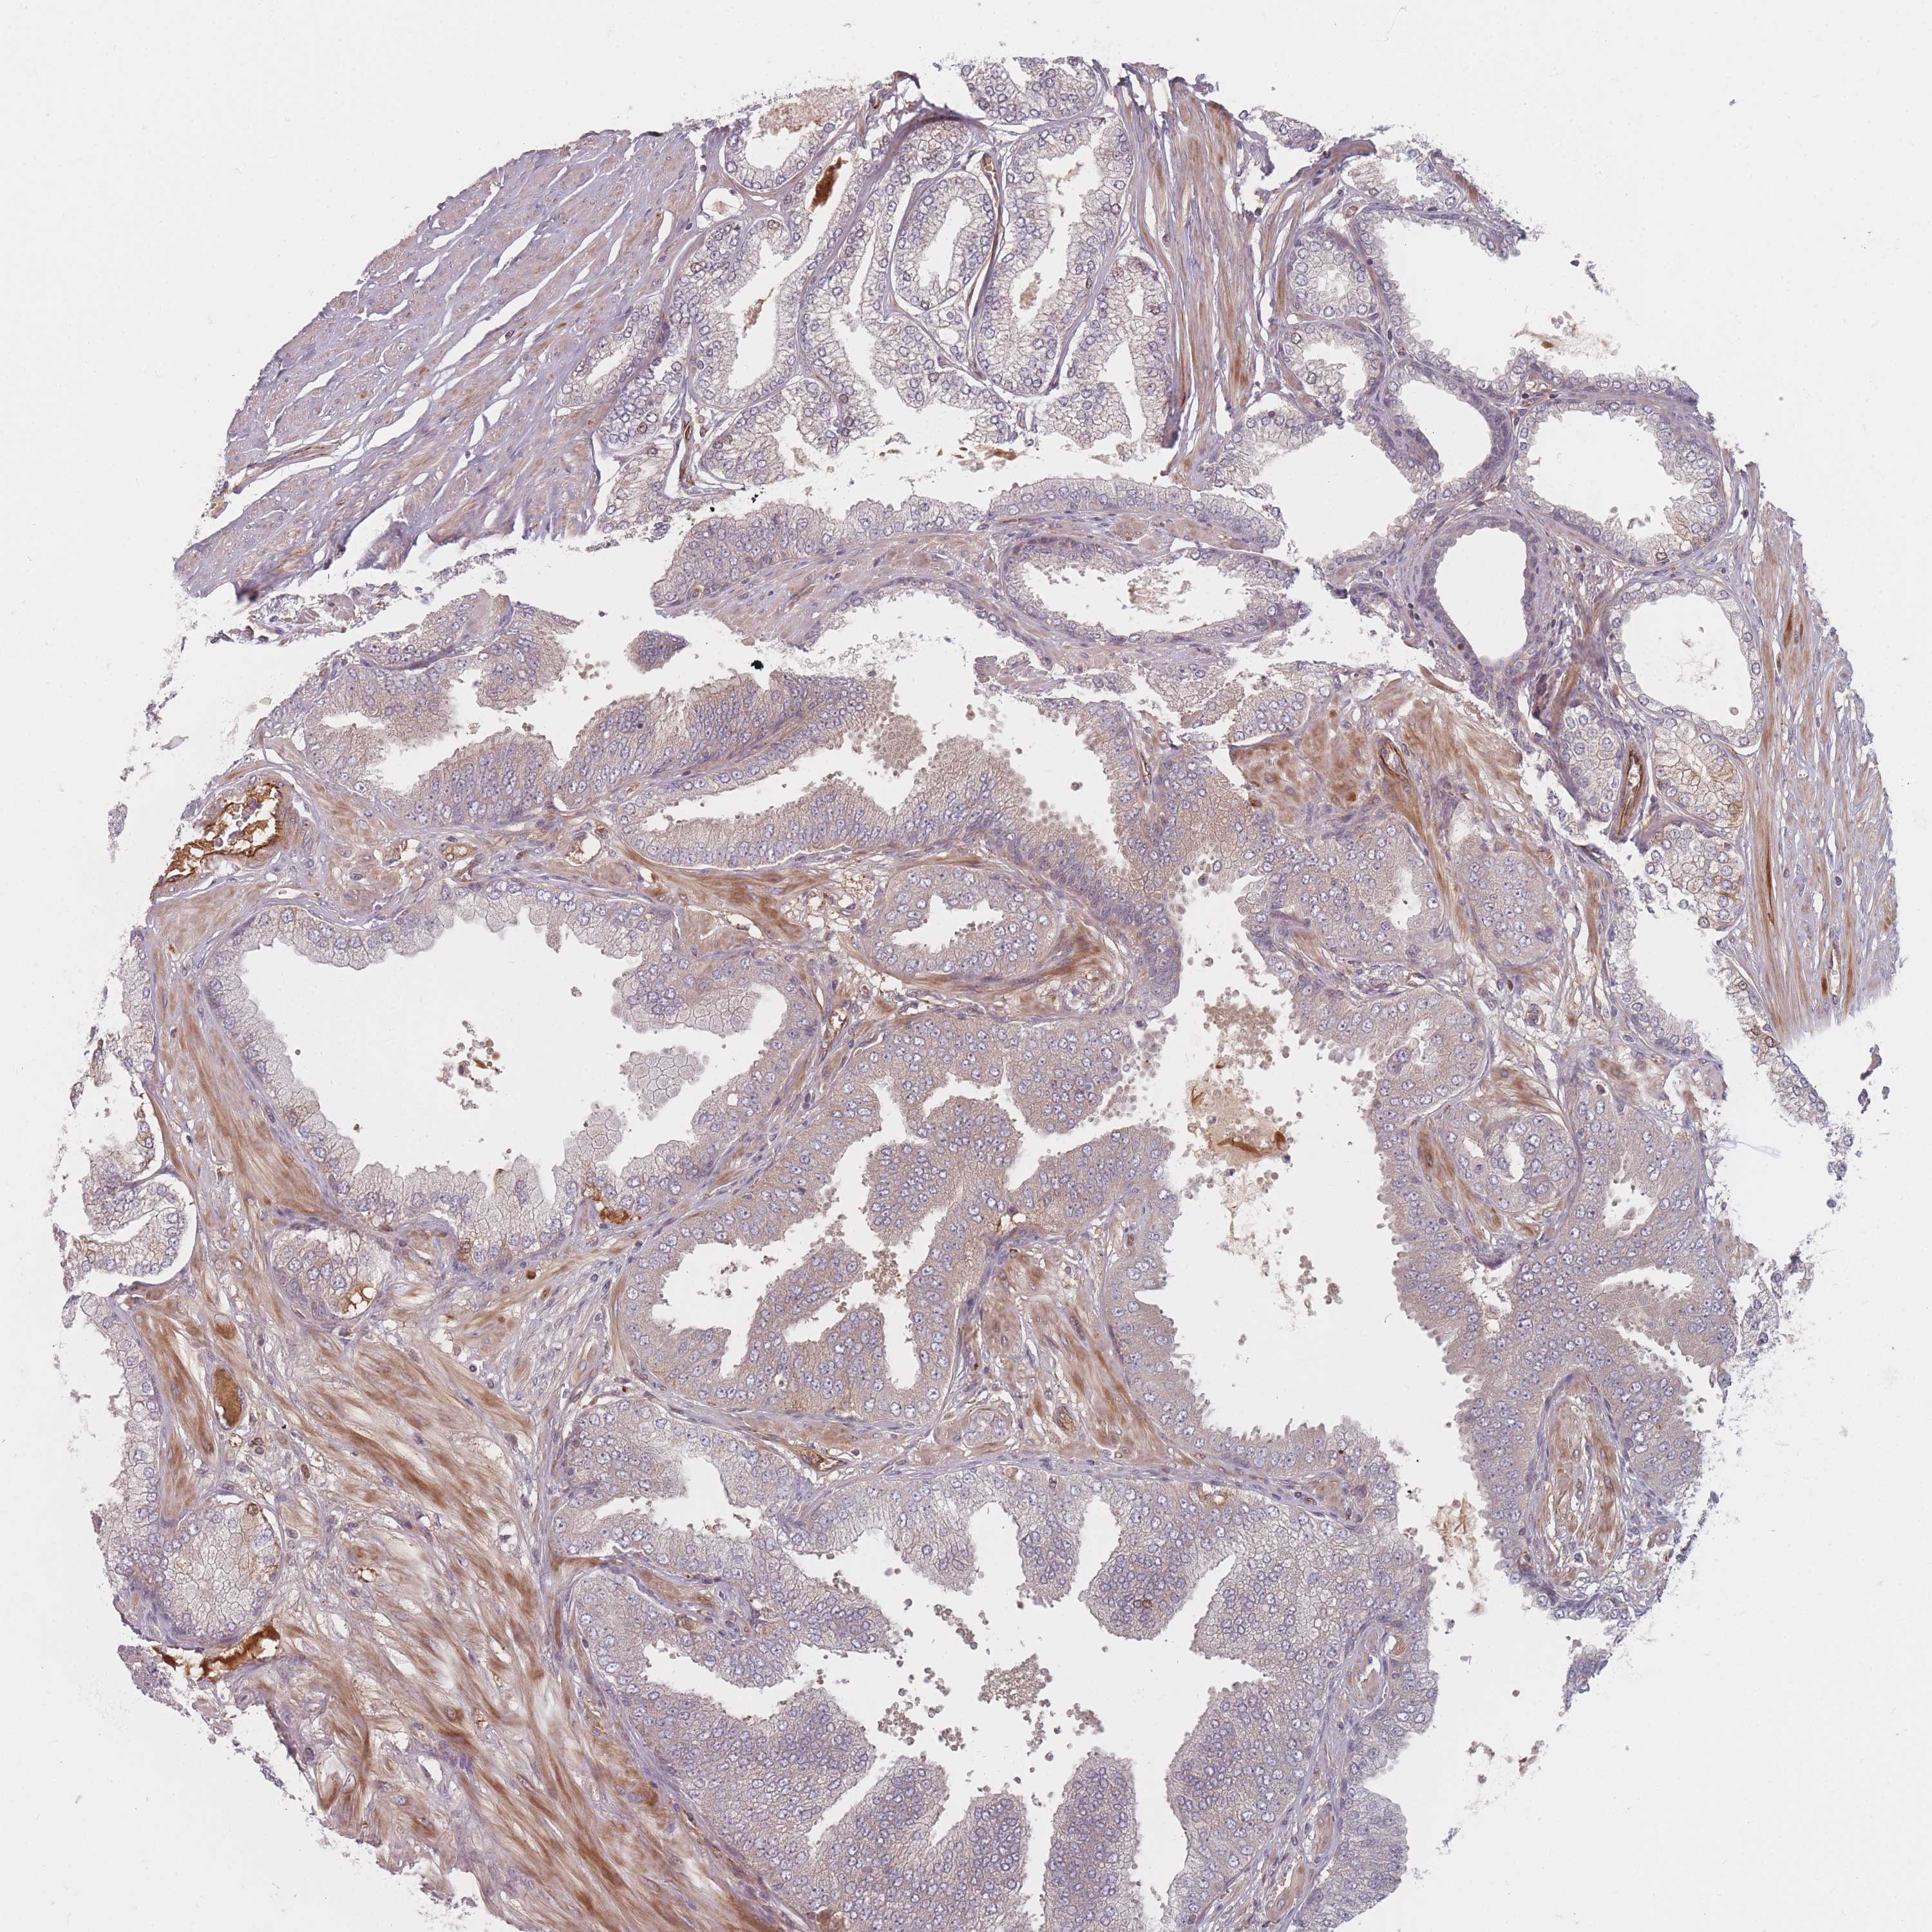

PROSTATE CANCER - Protein expressioni

A mouse-over function shows sample information and annotation data. Click on an image to view it in a full screen mode. Samples can be filtered based on level of antibody staining by selecting one or several of the following categories: high, medium, low and not detected. The assay and annotation is described here.

Note that samples used for immunohistochemistry by the Human Protein Atlas do not correspond to samples in the TCGA dataset.

Antibody stainingi

Antibody staining in the annotated cell types in the current human tissue is reported as not detected, low, medium, or high, based on conventional immunohistochemistry profiling in selected tissues. This score is based on the combination of the staining intensity and fraction of stained cells.

Each image is clickable and will lead to virtual microscopy that enables deeper exploration of all samples and also displays staining intensity scores, fraction scores and subcellular localization as well as patient and tissue information for each sample.

Antibody HPA050138

Staining

High

Medium

Low

Not detected

Intensity

Strong

Moderate

Weak

Negative

Quantity

>75%

75%-25%

<25%

None

Location

Nuclear

Cytoplasmic/membranous

Cytoplasmic/membranous,nuclear

Adenocarcinoma, High grade

Adenocarcinoma, Low grade